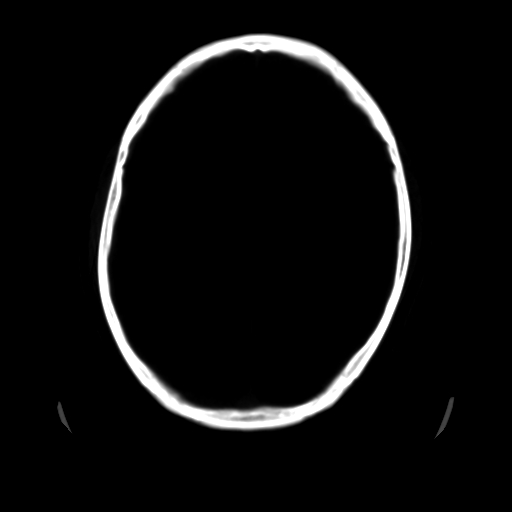

男,51岁,头外伤一小时,呕吐两次。

1)左侧中颅窝蝶骨翼后方硬膜外血肿。2)左侧颞顶部硬膜下血肿。3)蛛网膜下腔出血。4)左侧筛窦及双侧蝶窦炎症(或积血)。5)左侧额部头皮软组织肿胀。